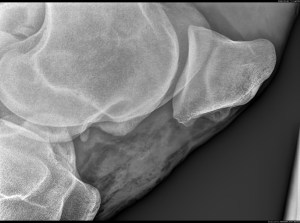

A day later, the fragment had moved to an area where it was even more visible. Another surgery wasn’t possible right away, the risk of a severe inflammation would have been to big. The next arthroscopy would be possible in about one month. It took a few days for the inflammation to subside. Maybe the third piece of cartilage had caused it, maybe the fact that one of the pieces was difficult to remove. The problem with these chips is that they can hide in some folds of tissue and are not visible on the x-ray. In order to be able to move around the arthroscope, the joint is inflated with liquid or gas. This had probably caused this third fragment to come out of its hiding place. Anyway, I felt miserable. I was sure that I would help my horse get better, and now it looked like the problem was still there, he was in more pain than before, and we didn’t know if this chip, floating around the joint, would end up in a place where it was operable. He would have to stay in his box for one month to wait for the next surgery. On the other hand, if the joint had not been that swollen and painful, we would have assumed that everything was fine, I would have started to train again after three months of rehab, just to find out that there still is a problem. Possibly, I wouldn’t have noticed anything right away and the chip would have caused more damage. The following pictures were taken during the surgery and they show how these chips have damaged the cartilage: